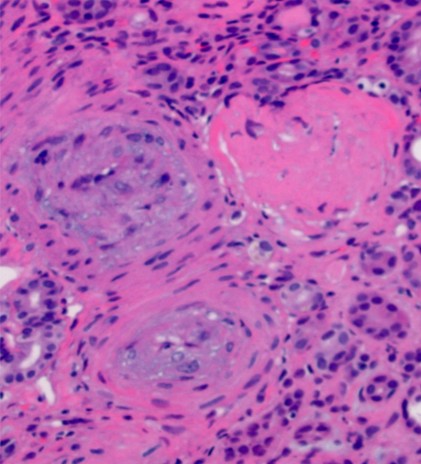

🫘Severe hypertension, Kidney: ⭐️Myxoid intimal hyperplasia of arteries (left, H&E), the lumens are reduced to pinpoint slits 💡Onion skin thickening of the arteriolar wall (right, PAS) 🔬Both images contain a sclerotic glomerulus – the end-effect of chronic ischemia #PathTwitter